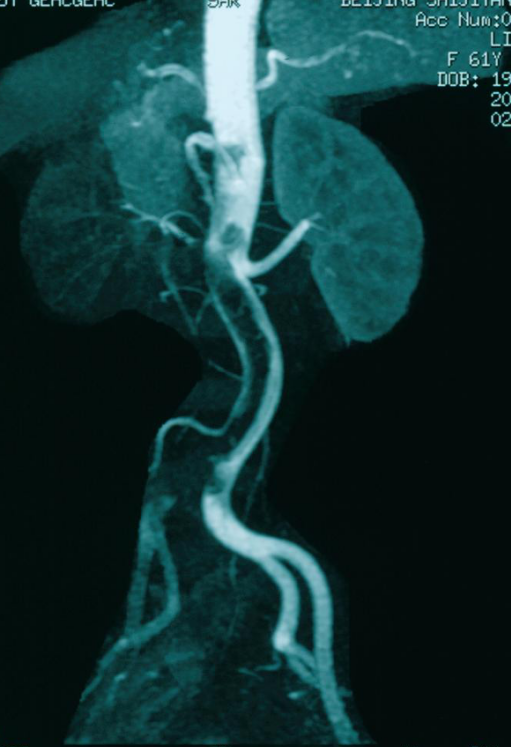

女性、80岁,诊断为主-髂动脉闭塞

通过预置导管溶栓成功开通闭塞段,术后血流恢复,治疗效果满意。